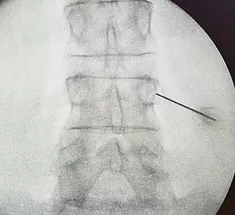

Процедура проходит под постоянным рентгенологическим контролем поэтому максимально безопасна для пациента.

На рентгене справа показано положение иглы в области медиальной ветви, иннервирующей межпозвонковый сустав.